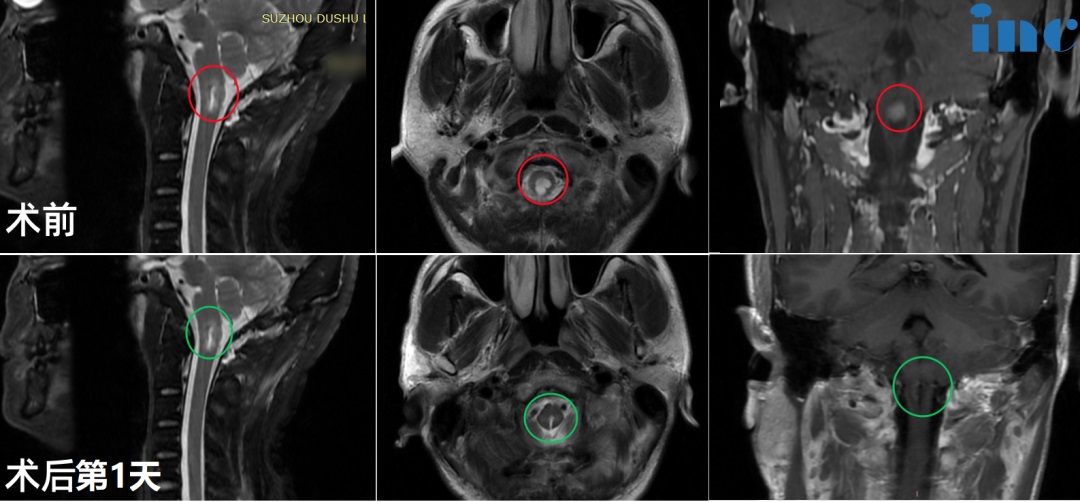

48岁男性-延髓海绵状血管瘤

术后1年,宋先生和巴教授进行了一次面对面的随访,他再次向巴教授表示了感谢!并接受INC专访,表示对手术治疗结果很满意,现在已经完全跟正常人一样的生活